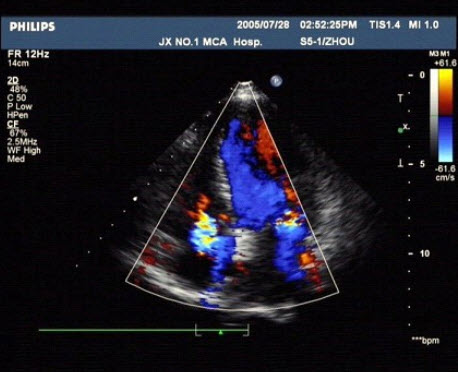

194、单项选择题

女,25岁,停经37周,阴道不规则出血来院就诊,B超检查声像图如图所示,最可能的诊断为()

A.胎盘早剥

B.前置胎盘

C.副胎盘

D.胎膜破裂

E.以上都不是